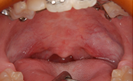

下顎骨の腫瘍で下顎を切除し(写真左)、切除したところを腰骨で再建し(写真中央)、インプラントを支えにしたブリッジ(写真右、白い部分)でかめるようにした症例のエックス線写真